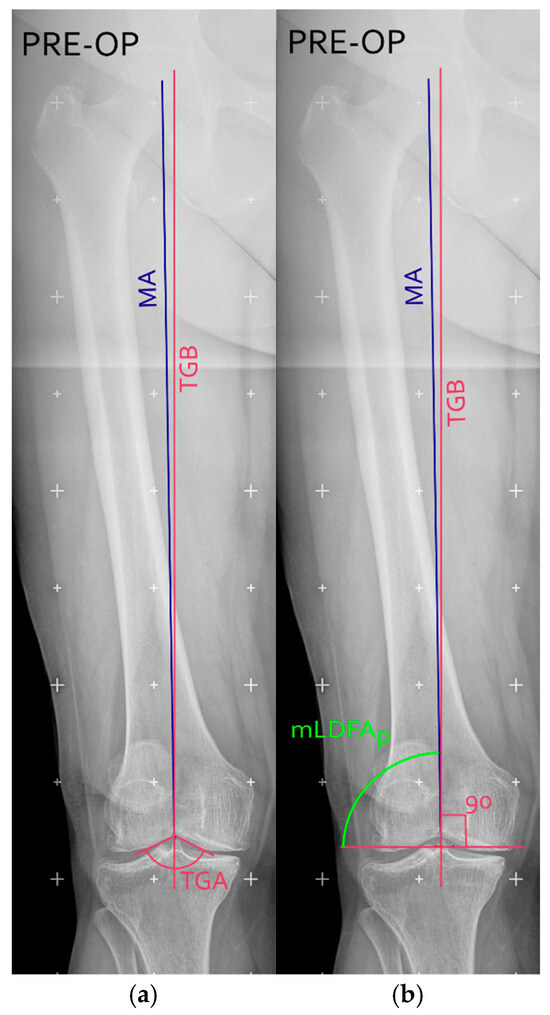

Background/Objectives: This study introduces and evaluates a novel surgical technique for total knee arthroplasty (TKA) that uses the trochlear groove bisector (TGB) as an anatomical landmark to achieve kinematic alignment of the femoral component in the coronal plane. The aim of the [...] Read more.

Background/Objectives: This study introduces and evaluates a novel surgical technique for total knee arthroplasty (TKA) that uses the trochlear groove bisector (TGB) as an anatomical landmark to achieve kinematic alignment of the femoral component in the coronal plane. The aim of the present retrospective observational analysis was to assess the reproducibility and accuracy of this approach and to report preliminary clinical outcomes. Methods: Twenty-eight TKA procedures were performed using the TGB-guided alignment technique. Preoperative planning and postoperative assessments were conducted on long-leg weight-bearing radiographs to measure the agreement between planned and achieved alignment, analysed using Bland–Altman statistics. Functional outcomes were evaluated at 12 months with the Knee Society Score (KSS), Forgotten Joint Score (FJS), and patient satisfaction. Results: The mean difference between planned and post-operative mLDFA was −0.3° ± 0.65°, with a root mean square error (RMSE) of 0.7°, demonstrating high accuracy and reproducibility. Postoperative outcomes showed mean KSS (knee = 89.6, function = 91.4), FJS = 69.6 ± 12, mean flexion = 124.6°, and mean HKA = 178°. Ninety percent of patients reported being satisfied or very satisfied at 12 months. Conclusions: The TGB-based technique offers a reliable, easily applicable method for restoring native femoral alignment in TKA using standard instrumentation. It allows accurate prediction of postoperative alignment and achieves favourable early functional outcomes. While currently limited to moderate varus deformities, future developments integrating 3D or CT-based planning may extend its applicability to more complex cases. Full article